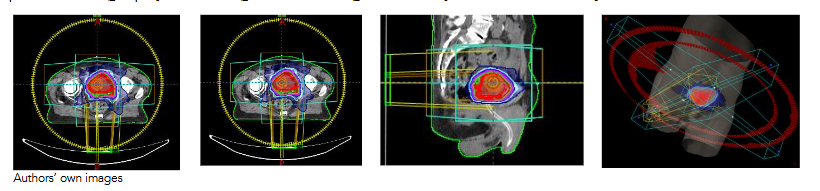

With this apparatus, three scenarios were generated with 1) all plugs inserted, 2) inner plug being out, and 3) no plugs inserted to the Arc Check system. Then, an MLC delivery pattern was selected based on an anonymized patient plan shows in

Figure 2, Treatment plan dose delivery pattern selected for this study.

, which displays a 2 Arcs VMAT plan. In this figure, the dose distributions around the treatment target were showed in 3 different views from a patient computed tomography (CT) image set. The right-side image is a 3-dimensional view. The two Arcs were modulated with the target volume shape. To implement the dose requirement, both delivery aperture and delivery speed were controlled with a complexity of multi-leaf collimator, optimal operation of the gantry rotation and varying dose rate provided by a modern linear accelerator (LINAC), which is a TrueBeam LINAC manufactured by Varian Medical System.